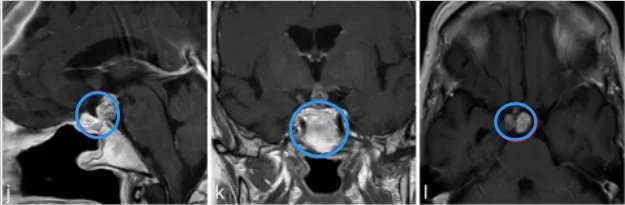

84岁女士视力减退。检查发现双侧视力下降、视野缺损。内分泌评估显示垂体功能完整。

a–c图中,MR成像显示鞍上部分实性,部分囊性对比增强病变,高度可疑的颅咽管瘤。

j-l图表示,在3个月后复查MR检查,显示术后垂体柄处有肿瘤少量残留。